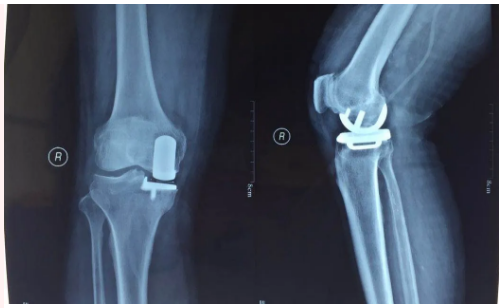

膝關(guān)節(jié)置換

嚴(yán)重膝關(guān)節(jié)疾病導(dǎo)致全膝破壞的終極治療是膝關(guān)節(jié)置換,骨二科采用內(nèi)軸膝系統(tǒng),能更好的模擬膝關(guān)節(jié)的正?;顒?,完美恢復(fù)膝關(guān)節(jié)的功能,達(dá)到Forget knee的效果。